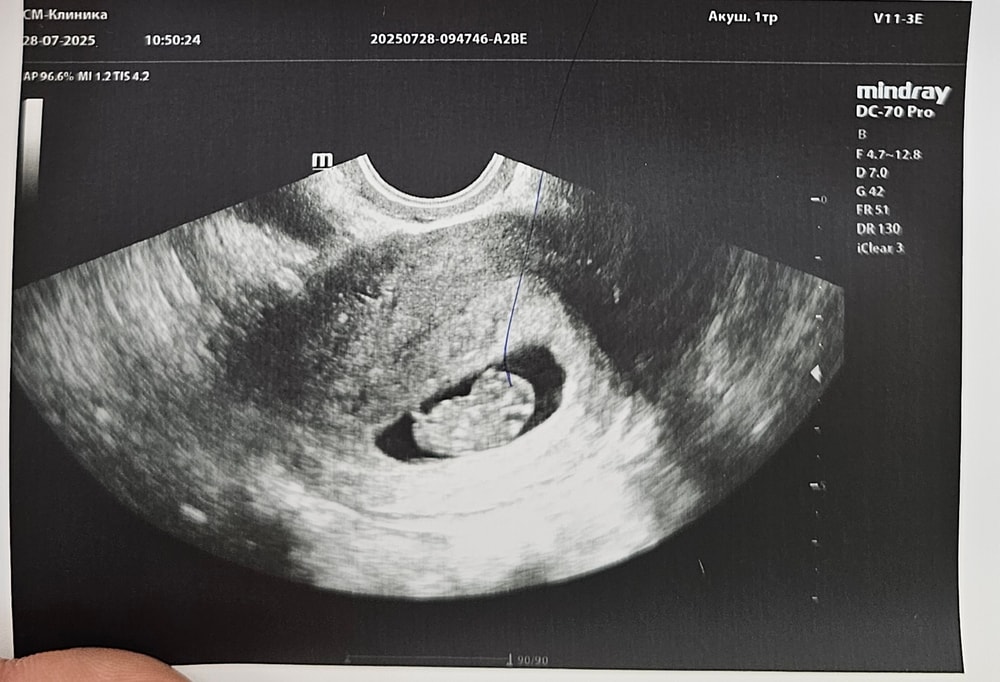

Сходила на узи. Срок по мес 9 нед + 3 дня. По узи поставили 9 +1. Растёт быстро, по овуляции я думала срок 8,5 +-. Матка по размерам на 9+ недель не очень тянет, но врач сказала, что так бывает и детки растут скачками. Срок поставила по ктр.

Ктр 21 мм

Жм 6 мм

Чсс 175 уд/мин